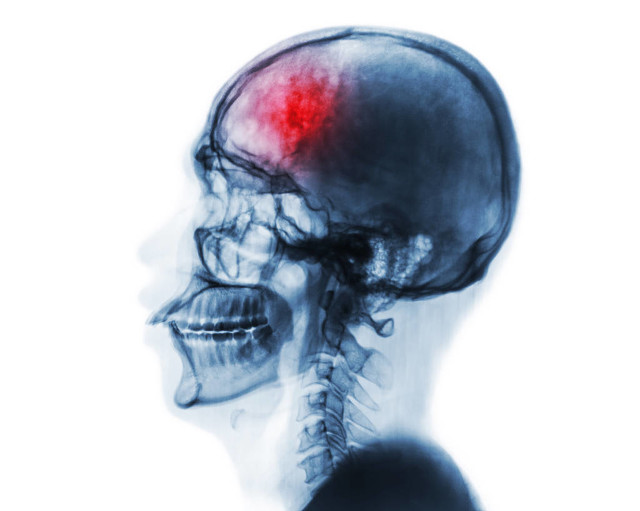

脑血管疾病是一类致残率很高的疾病,包括范围比较广泛,临床也很常见。

脑血管疾病现在发病年龄趋于年轻化,可能和现在年轻人生活压力大,生活不规律有关。个人觉得应该重视预防,定期监测血压血脂,必要时可以适当口服活血祛瘀药物,选择成分简单,副作用小的药物口服。